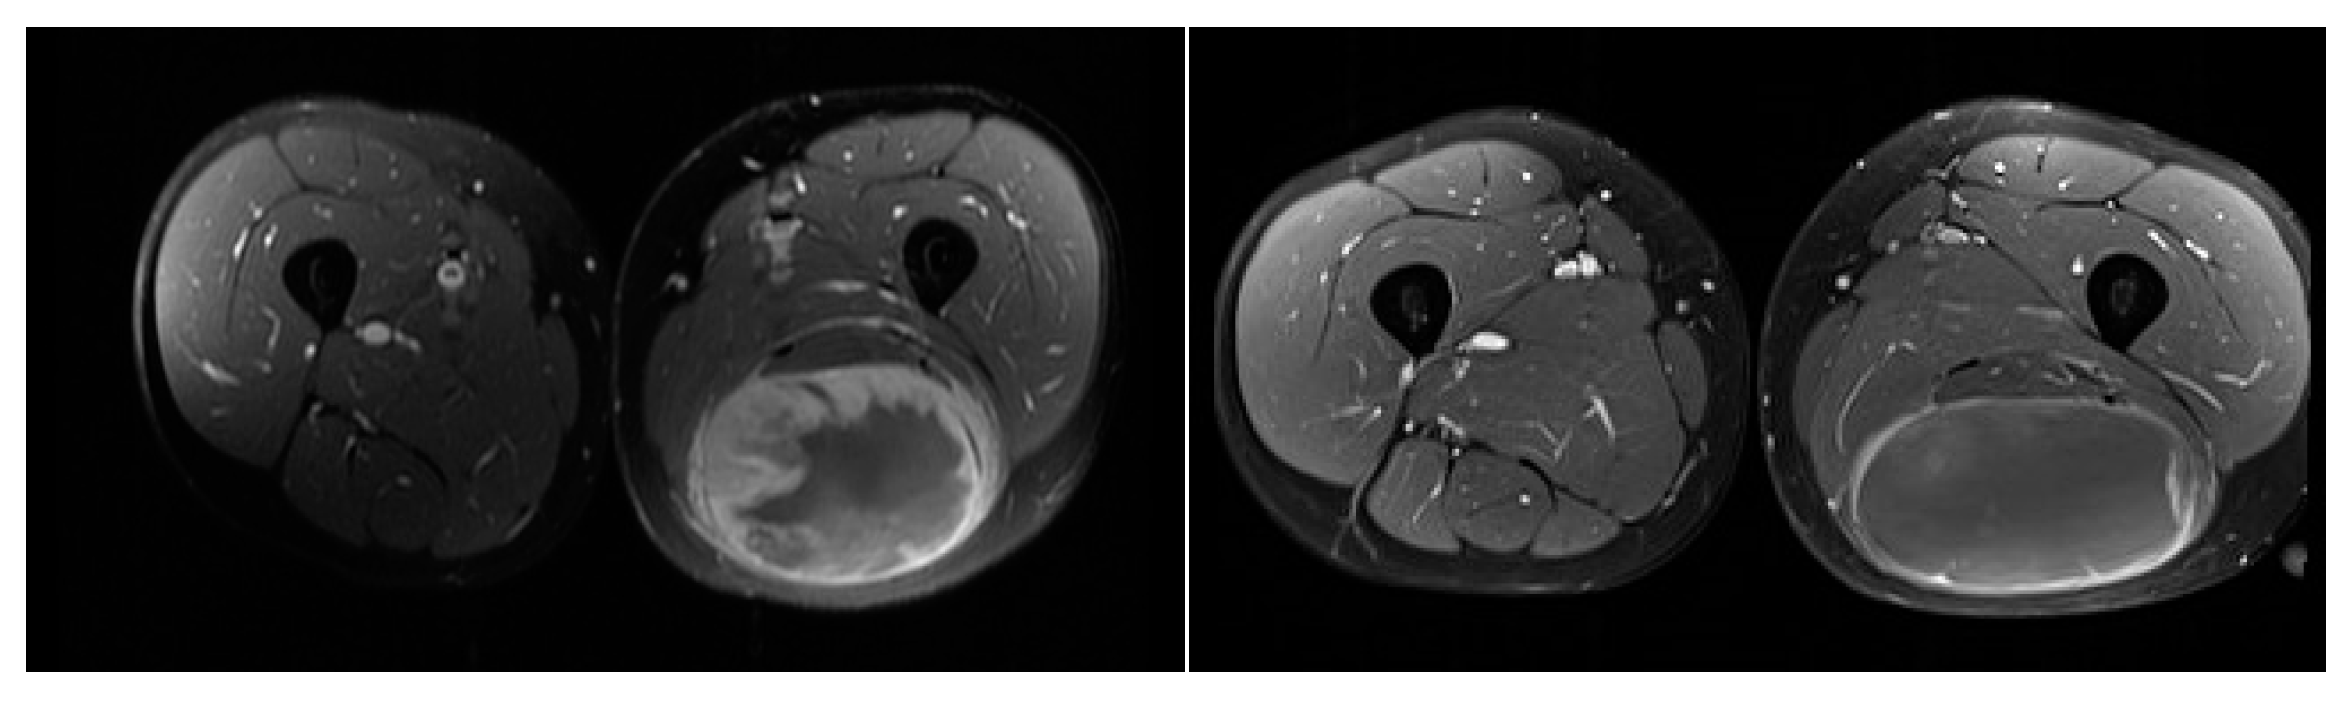

- Engstrom, K.; Bergh, P.; Cederlund, C.G.; Hultborn, R.; Willen, H.; Aman, P.; Kindblom, L.G.; Meis-Kindblom, J.M. Irradiation of myxoid/round cell liposarcoma induces volume reduction and lipoma-like morphology. Acta Oncol. 2007, 46, 838–845. [Google Scholar] [CrossRef]

- Kosela-Paterczyk, H.; Szumera-Cieckiewicz, A.; Szacht, M.; Haas, R.; Morysinski, T.; Dziewirski, W.; Prochorec-Sobieszek, M.; Rutkowski, P. Efficacy of neoadjuvant hypofractionated radiotherapy in patients with locally advanced myxoid liposarcoma. Eur. J. Surg. Oncol. 2016, 42, 891–898. [Google Scholar] [CrossRef] [PubMed]